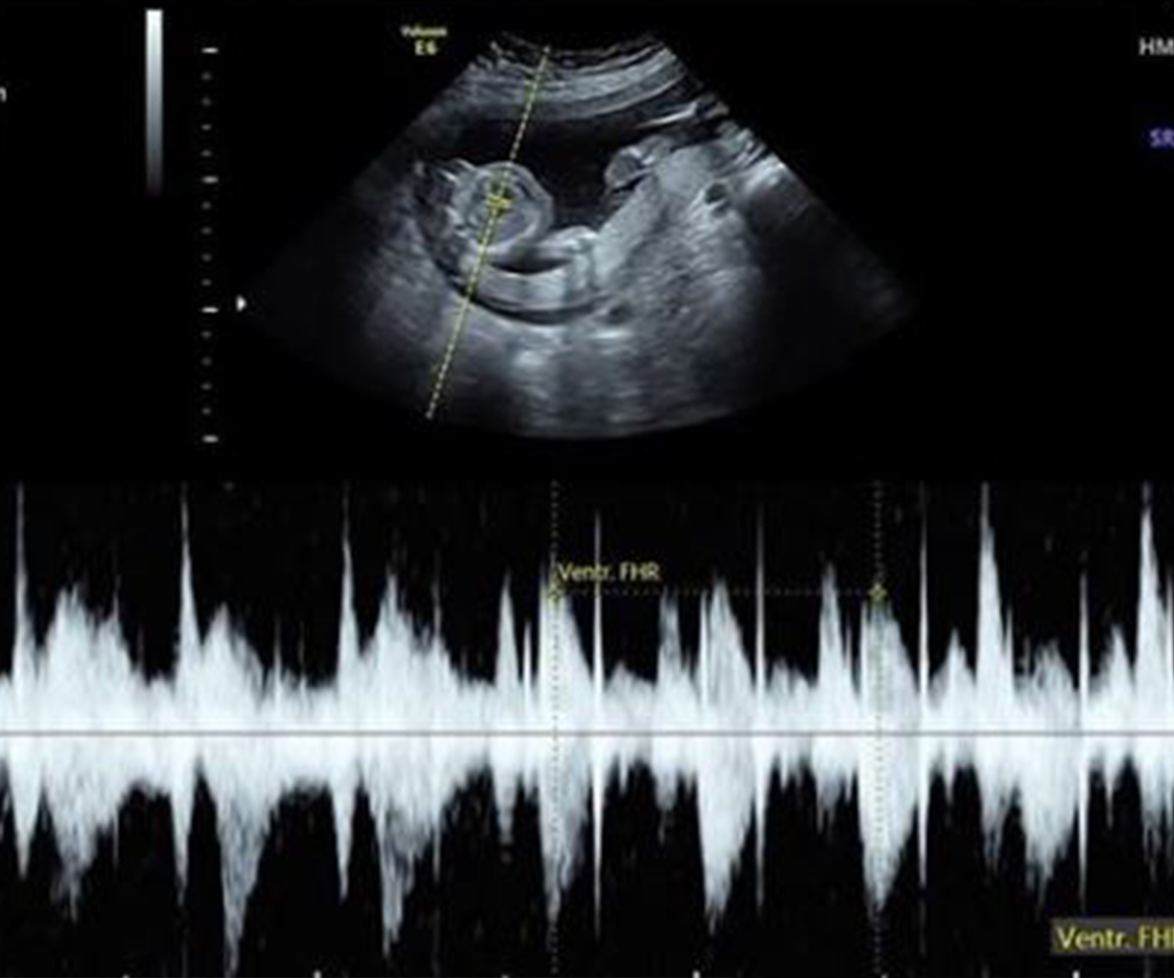

During Keri's pregnancy, the New Orleans couple were dealt the shocking blow that their unborn daughter was [terminally ill](http://www.nowtolove.com.au/news/latest-news/ada-nicodemous-stillborn-tragedy-6355 |target="_blank"), suffering from a birth defect called anencephaly, which means that her brain and skull will never fully develop.

It also meant that she would not survive more than a few days after her birth.

Baby Eva's heart is strong and healthy, but her brain and skull are not developing.